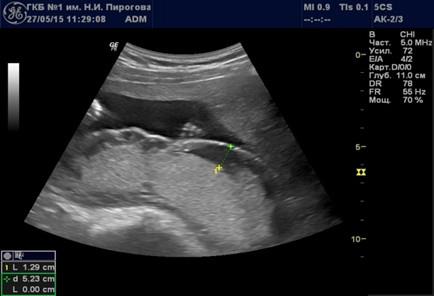

Рис. 7. Беременность 33 нед. Участок расширения межворсинкового пространства.